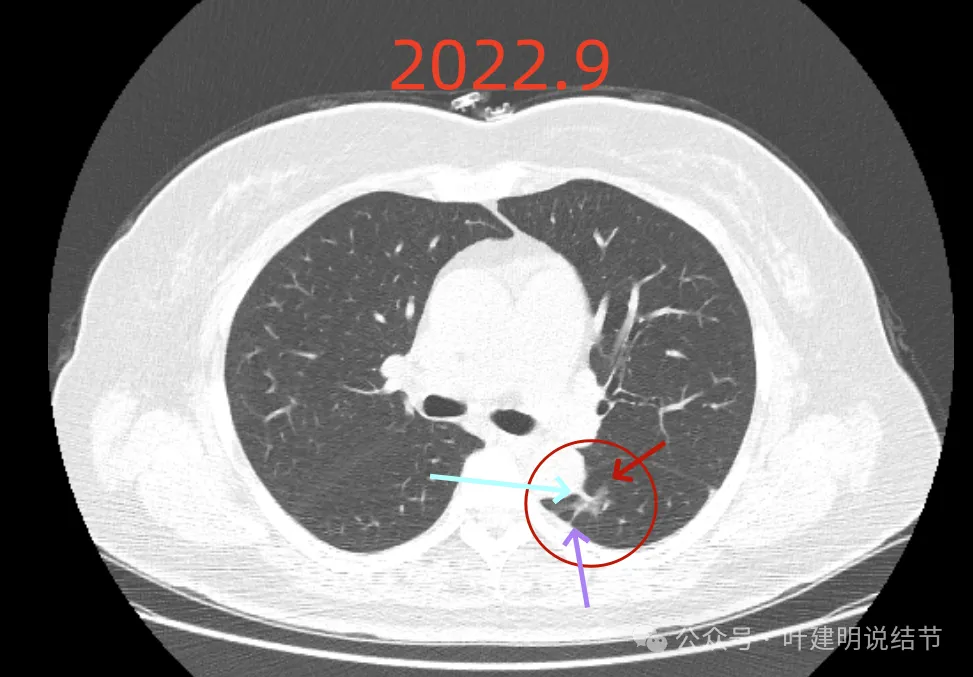

再看2022年的影像:

病灶磨玻璃密度,天蓝色这处密度高的条索状,紫色这处毛刺细长,病灶此层没有膨胀性,更像慢性炎伴纤维增生的样子。

密度不均,有实性成分了,表面分叶,但膨胀性仍不强。

基本实性密度,边缘较为平直,胸膜牵拉不显著。

病灶瘤肺边界稍显模糊,但与2019年时比,邻近胸膜增厚似乎不如之前明显。

从3年对比来看,由于没有吸收好转,也说不上显著展,虽恶性概率较前有所增加,但慢性炎或肉芽肿性炎仍可能的。谨慎随访也是可行的。当然现灶在边缘,若定要明确,微创手术也是可行的。或者查下PET,但这种几乎进展不明显的病灶,估计有代谢增高,一般也是轻度增高,仍不能完全明确性质的。